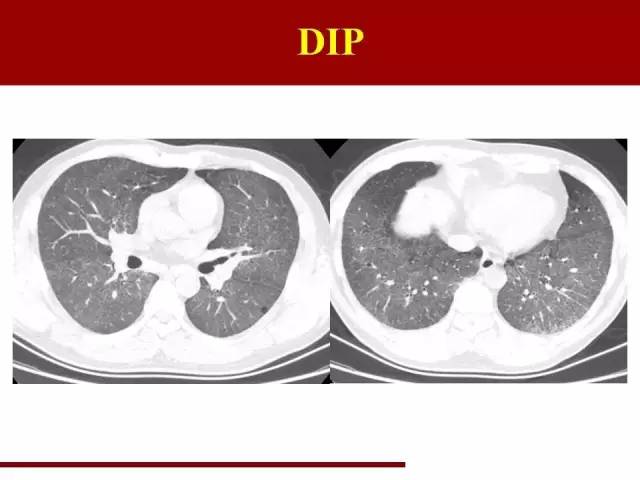

DIP诊断相对容易

从它曾用名就可以知道特点:脱屑型间质性肺炎,表现为肺泡腔内堆满了头皮屑的感觉

同时可以伴有小薄壁囊腔

以前病理认为DIP为细胞碎屑脱落至肺泡腔,现在的病理认为还是炎性细胞在肺泡腔内充填

同样是磨玻璃病变,DIP和NSIP表现就完全不一样,不一样在哪里呢?

NSIP磨玻璃影位于肺泡表面,是纤维的增生,所以有轻度网格状感觉

但是DIP的磨玻璃病变出现在肺泡腔,所以更有颗粒状感觉,也就是头皮屑的感觉